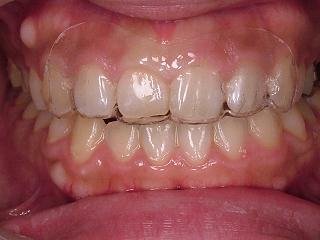

当医院でもよく行いますが、1~2歯だけを動かしたい場合には少し大袈裟になってしまいますので、写真の様に部分的に装着して頂き動かして行きます。

この患者さまは右上1番のみ前に出してラインを揃えます。

マウスピース矯正の症例